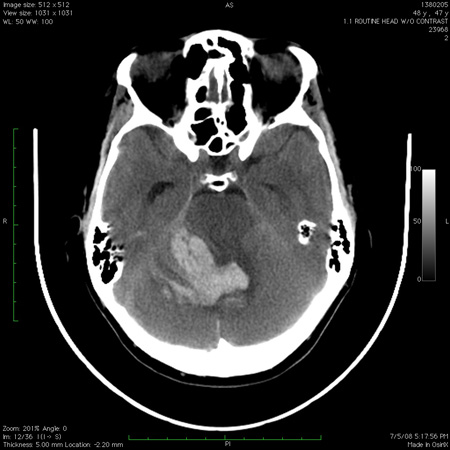

თავის ტვინის კომპიუტერული ტომოგრაფიის გამოსახულებაზე ჩანს ნათხემის ჰემორაგია, რომელიც მეოთხე პარკუჭში გადადის

ექიმი ს.ჰ. საბრამონის კოლექციიდან; გამოყენებულია მფლობელის ნებართვით